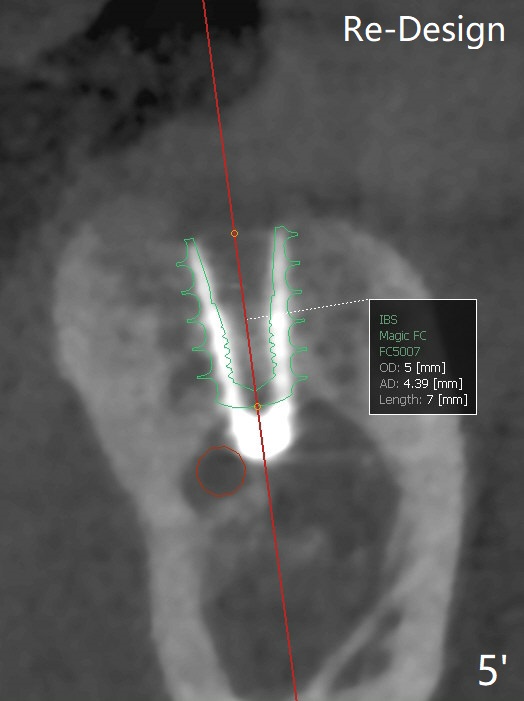

导板种植是否需要切开取决于牙槽嵴角化龈宽度,放置导板后,插入环形刀(图一),用手的压力(不要开手机)接触牙龈后,抽出环形刀,并且取出导板,检查环形标记是否累及颊侧粘膜(图二)。这个病例没有,所以没有切开,也没有保留角化龈(骨质硬,预计术后可以使用愈合基台)。在34毫克利多卡因17微克肾上腺素浸润(jinrun)麻醉下,完成钻洞(最后钻头3.5x10毫米),植体植入,拍摄CT却发现植体非常接近神经(图三,五),似乎钻洞向舌侧偏移(与设计(图四)对比),可能与没有远中牙齿固位有关。由于术中没有疼痛,估计没有直接损伤神经,放置愈合基台,在后者周围空间塞入骨粉(图六:*)。理想情景使用2.2x7.3毫米钻头后,拍摄CT,最后植入4.5或者5.0x7.3毫米植体(图五')。术后没有疼痛也没有麻木。